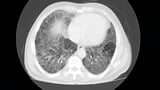

Nerandomilast Trial Shows Promising Results in Slowing Pulmonary Fibrosis Decline

The phase 3 FIBRONEER-ILD trial results indicate that the investigational oral agent nerandomilast significantly slows the decline in forced vital capacity (FVC) in patients with progressive pulmonary fibrosis (PF).

Nerandomilast is a PDE-4B inhibitor, which has shown antifibrotic and immunomodulatory effects in preclinical studies.